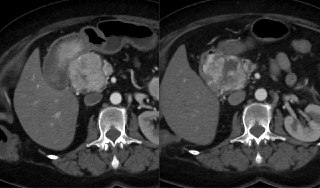

Як і обіцяли – докидаємо другу КТ яка виконана після декількох місяців терапії комбінації акситинібу та пембролізумабу. Давно та надійно відомо, що на метастатичну RCC стара добра цитостатичнка хімка працює поганенько, шоб не сказати ніяк. Але всілякі відносно новіші молекули справляються інколи дуже непогано. Особливість їх в тому, що вони не працюють прямо як молоток, а скоріше опосередковано через складні інгібіторні механізми, то «вимикаючи» пухлинкам можливість створювати васкулярзацію та позбавляючи їх харчування, то «демаскуючи» їх для власної іммуної системи і надаючи можливість їй самостійно активніше позбавлятись атипових клітин (тут прохання до онкологів та людей які шарять за молекулярку, не ображайтесь за максимальне спрощення).

Хочемо ми цього чи ні, але і на радіологічне відображення такий механізм дії має неабиякий вплив. Класична історія з зменшилося/збільшилося тут працює вкрай погано. Саме тому навигадували купу альтернатив топорному RECIST для таких сценаріїв. Користуєтесь ви будь якою системою з циферками чи нє, головне пам’ятайте, що підсилення та некрози важливіші за розміри в таких сценаріях.

Цей кейс також є непоганою іллюстрацією цього принципу. Погортати КТ після терапії яка демонструє відповідь на лікування можна ось тут.